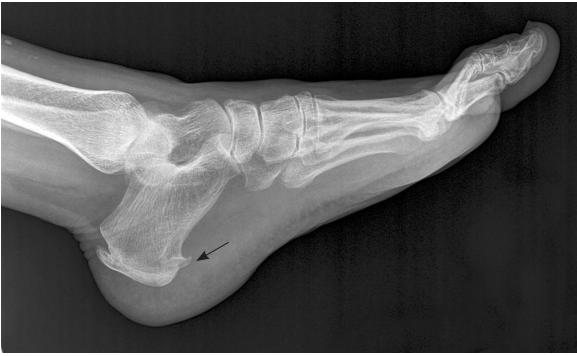

如果去医院拍片子,可能会发现如下图一般的跟骨骨刺(黑箭头所示)。

但是,一定注意:

并不是因为长骨刺,才得了足底筋膜炎。因为很多没有任何症状的人也会有这里的骨刺,而很多有足底筋膜炎的患者并没有跟骨骨刺。所以无论是疾病病因,还是后面的治疗,都跟这个骨刺没多大关系。哪些告诉你说能消骨刺治这个病的,别信就好。